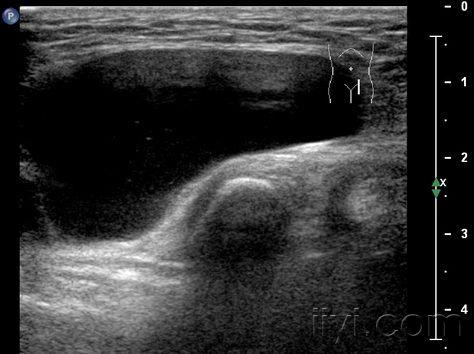

今天和同事做个腹股沟包块--失败告终!